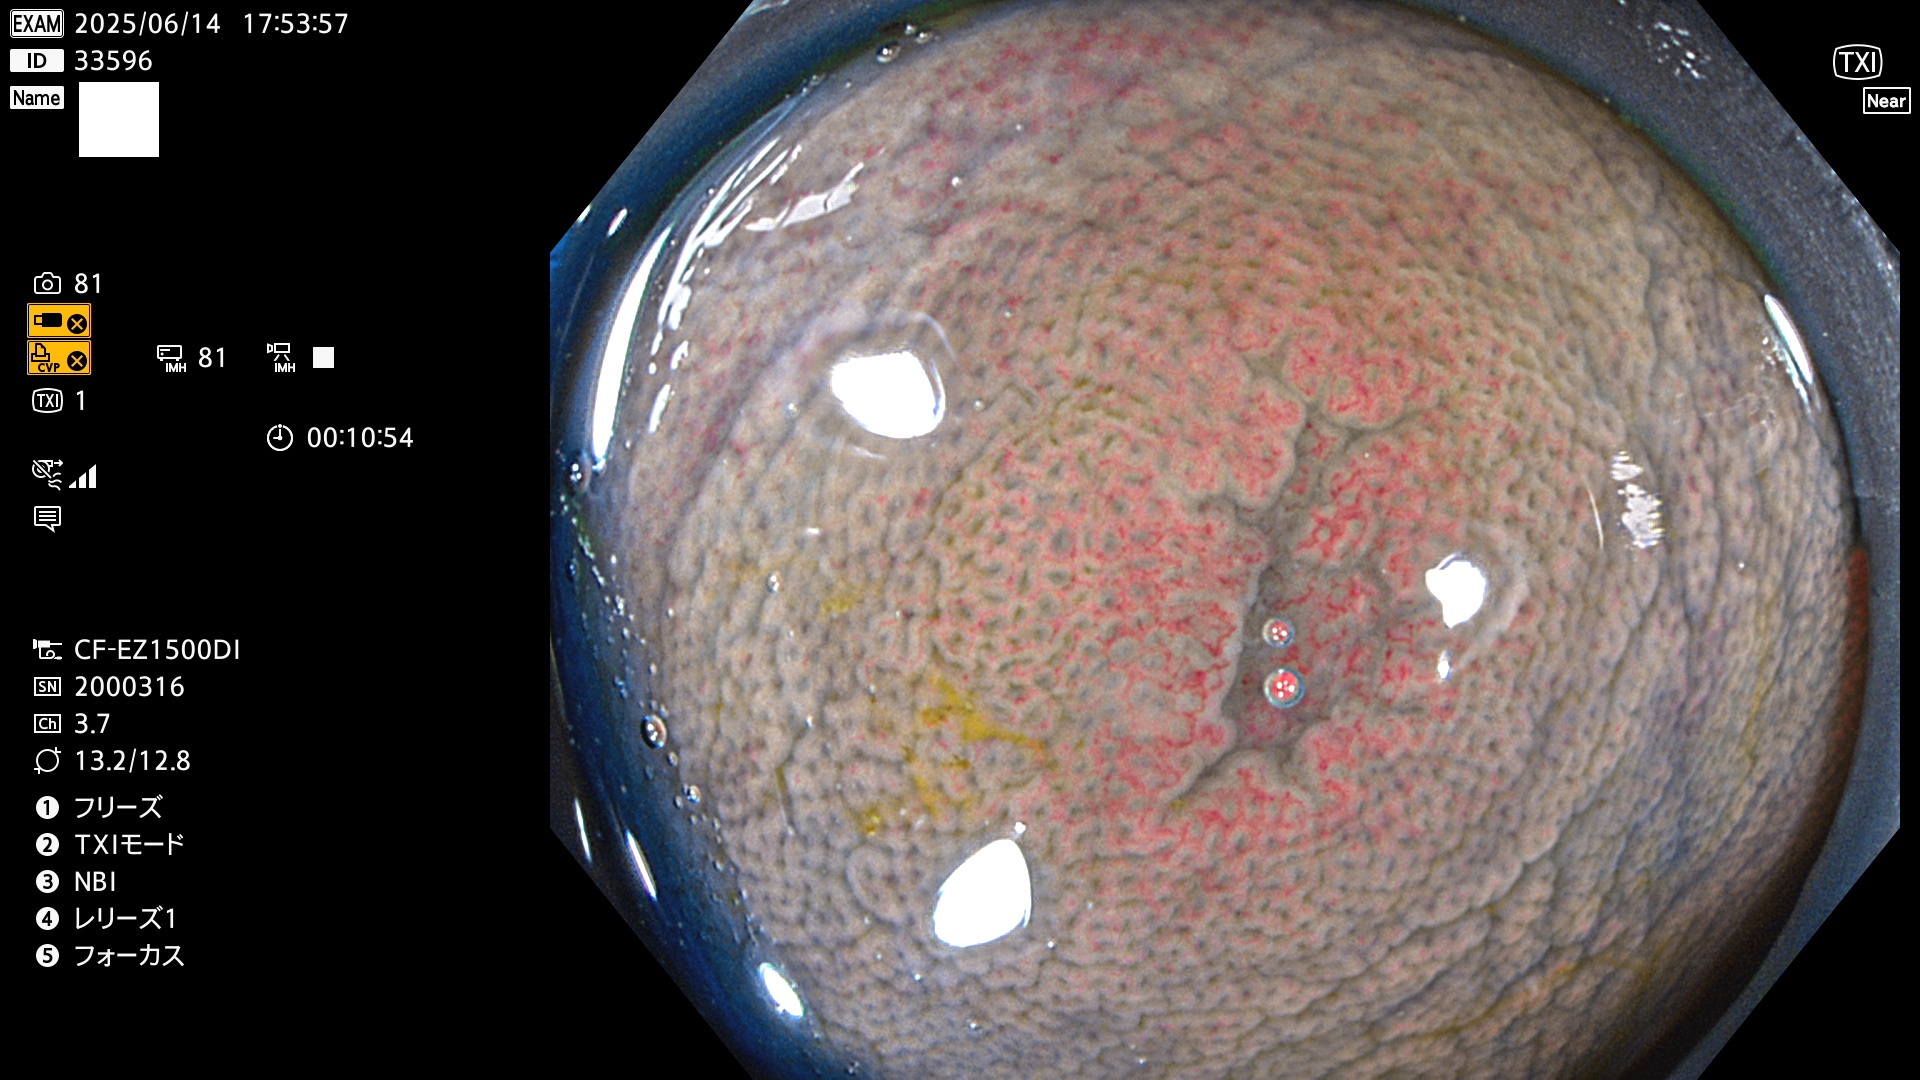

完全に平坦な物をUb、陥凹している物をUcと呼びます。Ubは認識が困難で、Ucはびらん(炎症)と紛らわしいために見落とされやすく、「内視鏡後・大腸癌」の原因になります。

抽出の対象期間 2025年6月12日〜6月15日の4日間(48件の検査)14個 (14/48=29%)